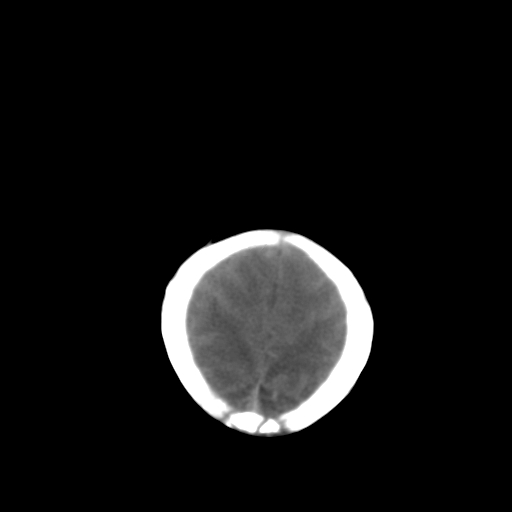

男,2天,孕31周早产儿,出生后窒息3分钟,精神反应差。

脑实质弥漫低密度,灰白质界限不清:结合临床考虑重度hie